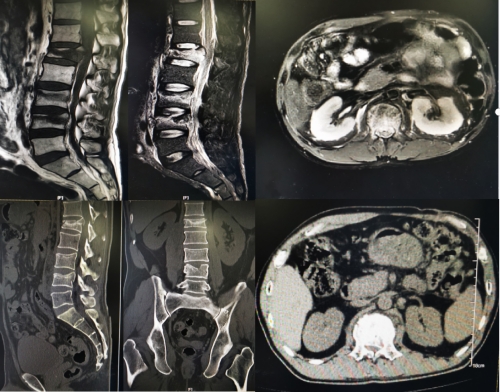

(手术前)

本次接受远程骨科机器人手术的是一位因高处坠落伤导致腰椎多节段爆裂骨折的男性患者,其中尤以L1椎体最严重,骨折块移入椎管内引起脊髓受压,万幸的是该患者没有明显的脊髓损伤表现。为了更微创同时更安全的解决患者病痛困扰,经邓幼文主任手术团队讨论,并与北京积水潭赵经纬主任沟通交流后,决定采用“两地协同,远程机器人诊疗”的方案,由湘雅三医院脊柱外科携手北京积水潭医院机器人远程手术中心,通过5G通信技术结合机器人开展远程手术。手术当天,邓幼文主任、李志跃主任、谭伟主治医师及刘仁峰总住院医师组成了湘雅三医院手术团队与北京积水潭医院赵经纬主任及其团队,在积水潭医院机器人远程手术中心实时连线交流指导,经过两个团队的精诚合作,手术得以顺利的开展,患者麻醉醒来即感痛症状缓解明显,检查并无神经损伤表现。